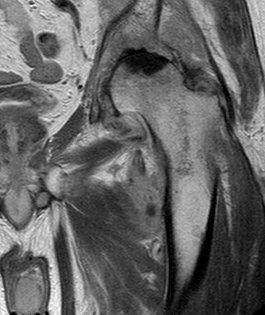

Patients usually present with a very rapid onset of severe pain and signs of toxicity. In patients who are very immuno-compromised there may not be the usual signs of systemic reaction to infection. In the early stages x-rays may mimic arthritis or AVN.

MRI is very sensitive but may still struggle to differentiate between advanced sepsis and AVN.